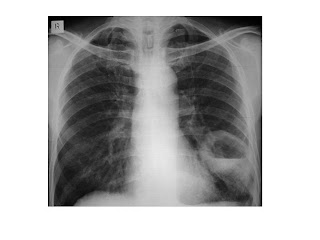

This program discusses the preventive, diagnostic and therapeutic measures indicated for lung cancer. The program notes that pre-cancerous lesions from smoking may be reversible and that periodic chest x-rays should be used as the primary diagnostic tool. Such pathologic conditions as ... View Video

However, the differential diagnosis is wide. Many other diseases can also give this appearance, including tuberculosis, fungal infections, Survival for lung cancer falls as the stage at diagnosis becomes more advanced: ... Read Article